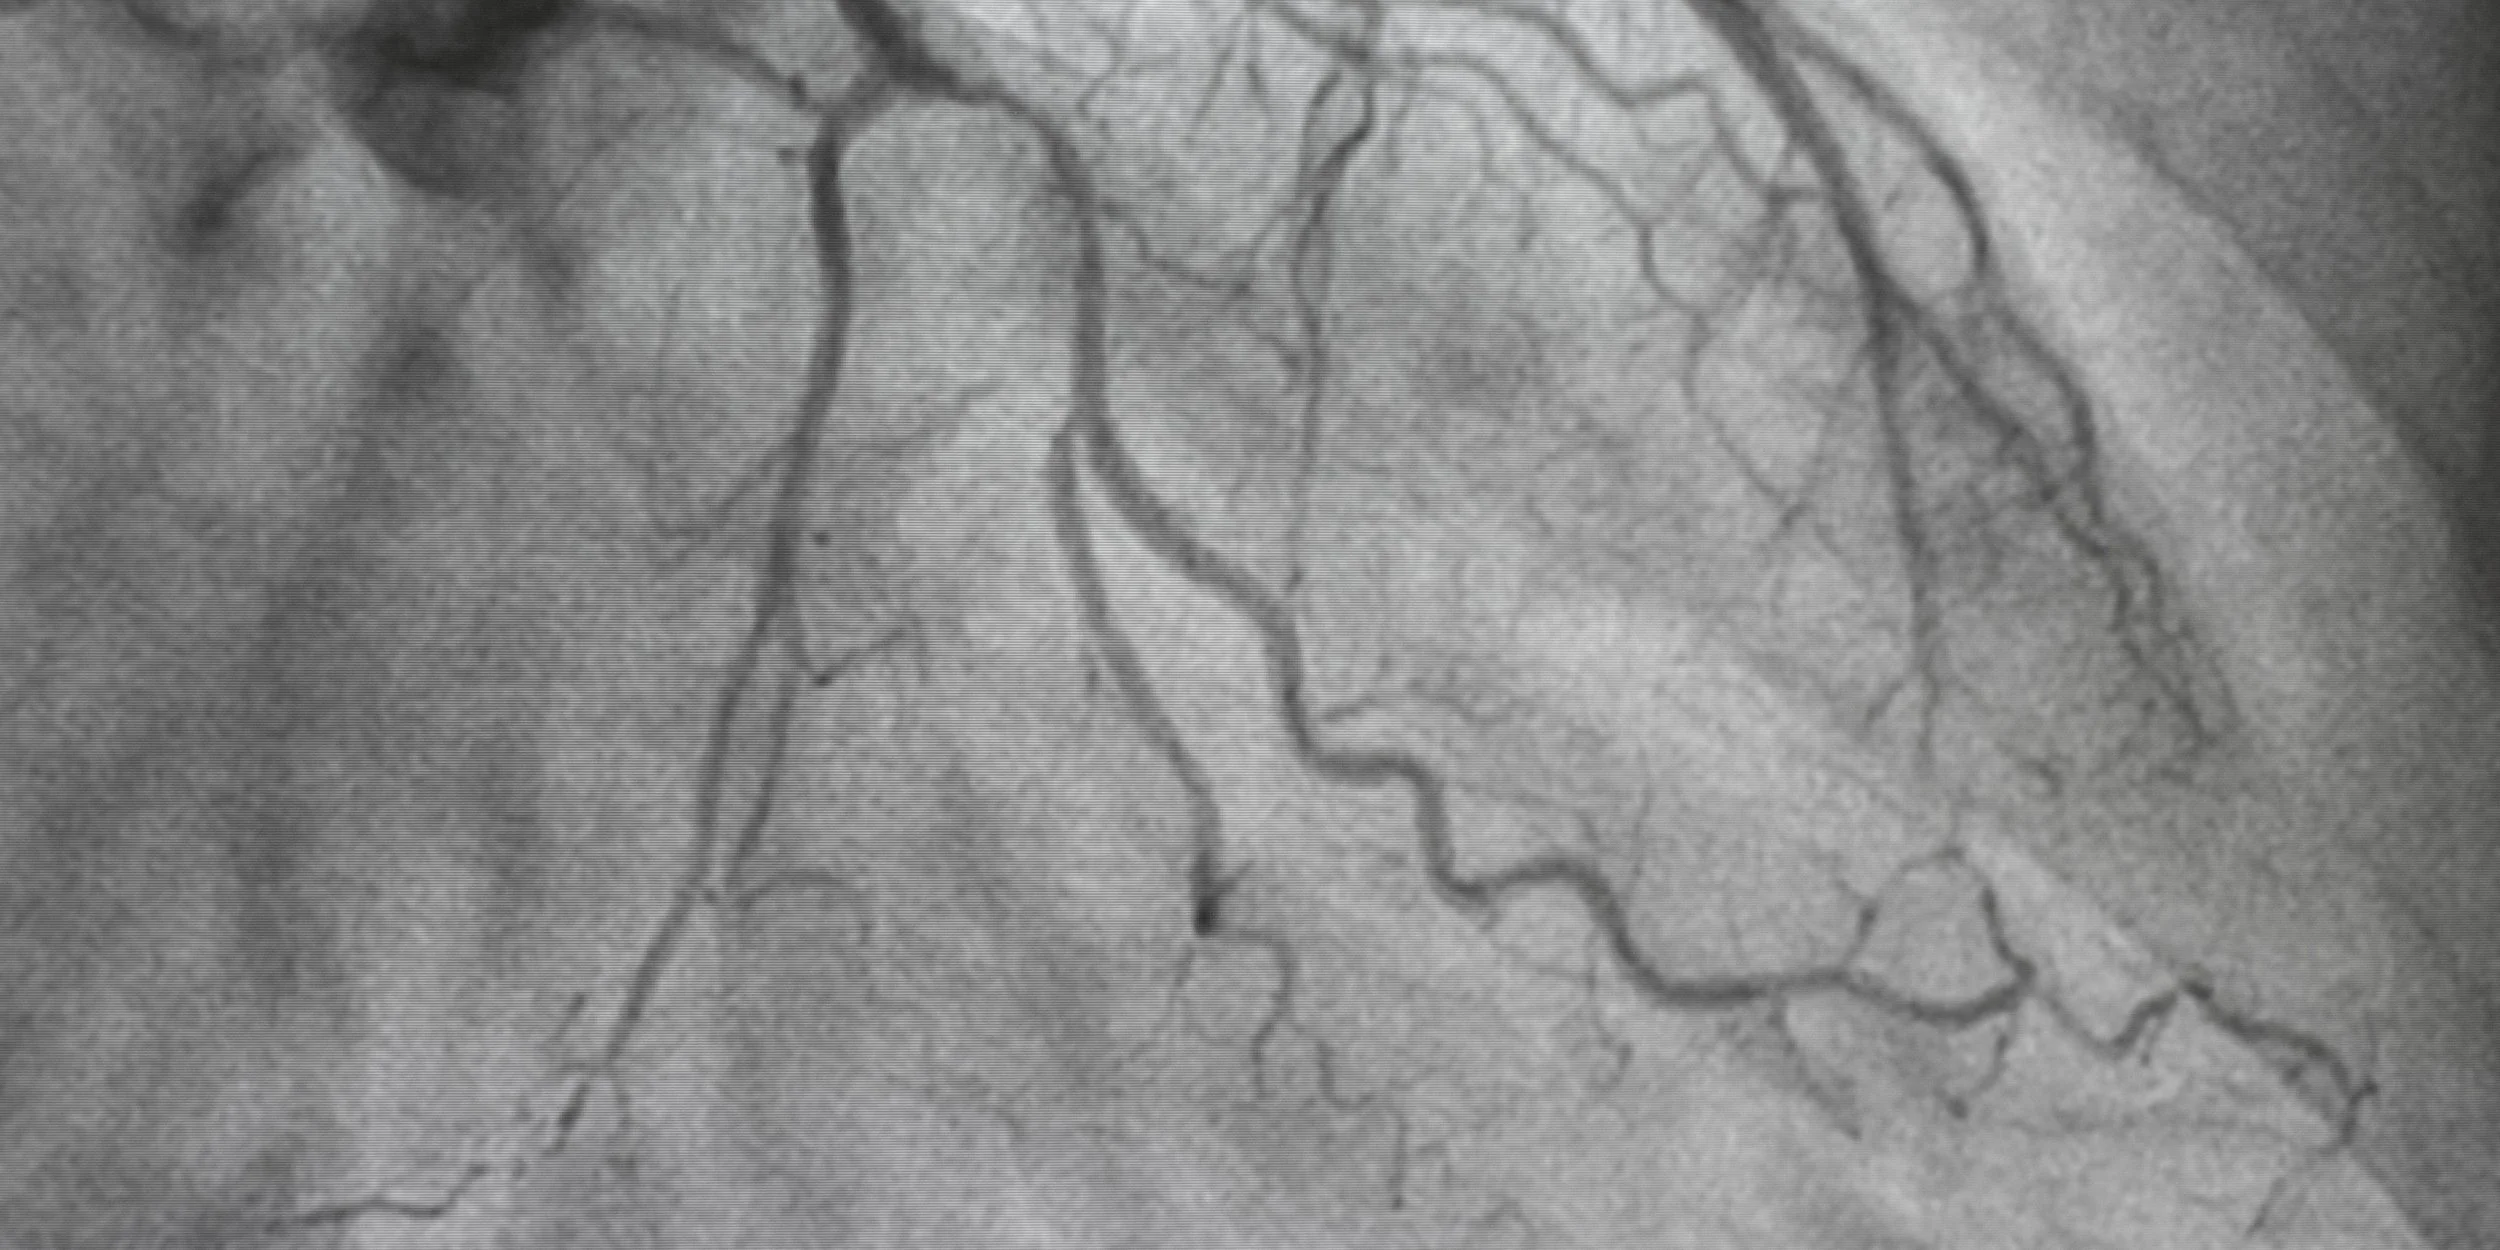

Coronary Angiography

A coronary angiogram is a test that allows us to see whether the arteries supplying your heart are narrowed or blocked. A small tube (catheter) is passed through a blood vessel in the wrist or groin, dye is injected so the arteries can be seen on X-ray. The procedure usually takes 20–30 minutes.

It’s done to investigate chest pain or breathlessness after an abnormal CT scan or stress test or following a heart attack or suspected heart disease.

✔ Usually done as a day-case

✔ Local anaesthetic, you are awake but comfortable